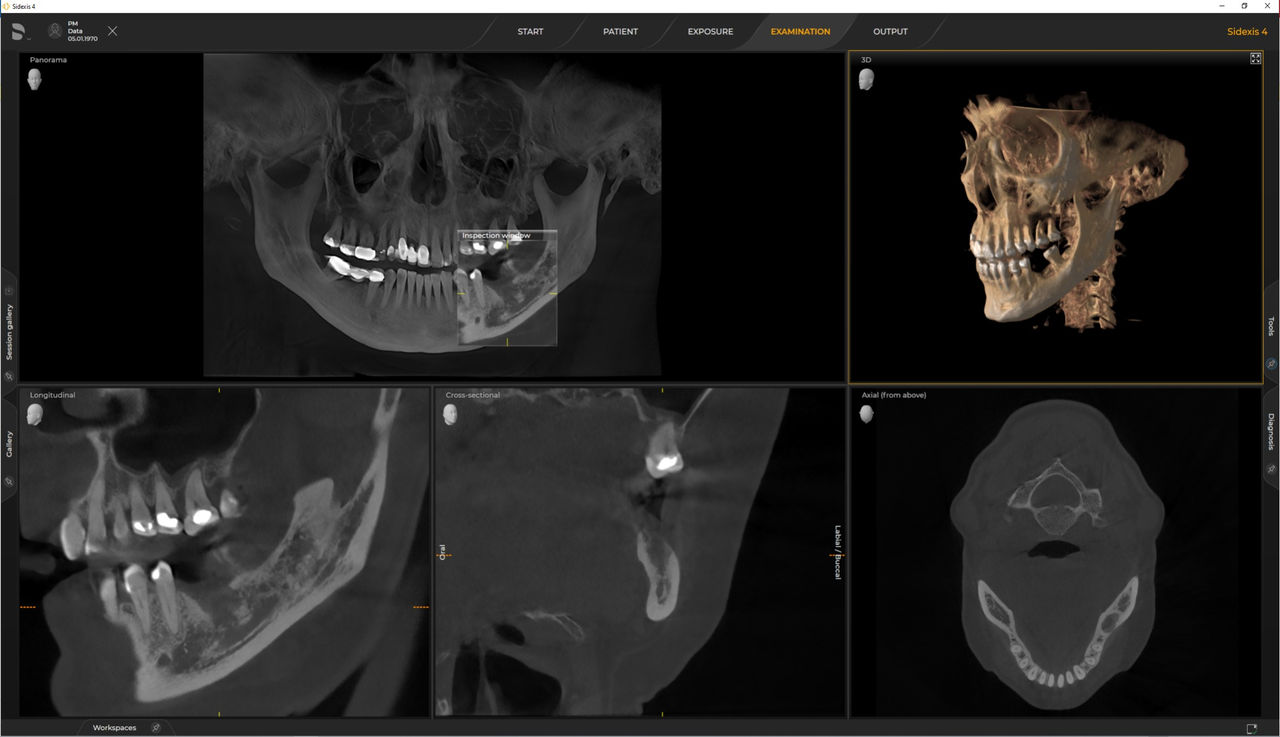

Axeos, el sistema especializado 2D/3D con un gran volumen y alta calidad de imagen para clínicas con una amplia oferta de tratamientos. Desarrollado junto a dentistas y clínicos, Axeos ofrece la gama más completa de funciones de todos los equipos de radiología extraoral de Dentsply Sirona. Además de una excelente calidad de imagen y tamaños de volumen 3D personalizados, el equipo de radiología dental está completamente optimizado para una mayor comodidad del paciente. Axeos no solo proporciona calidad en rendimiento y comodidad, sino también con su galardonado diseño gracias al gabinete integrado para el almacenamiento de posicionadores de mordida y la luz ambiental.

Los requisitos siguen aquellos del software de procesamiento de imágenes de Sidexis 4 y Axeos. Para obtener más detalles, consulte los requisitos del sistema Sidexis 4 y los requisitos de instalación de Axeos.

Las unidades 3D de Dentsply Sirona funcionan exclusivamente con Sidexis 4. Sin embargo, la migración de datos de Sidexis XG a Sidexis 4 es muy fácil. Sidexis 4 permite una experiencia digital completa con las últimas herramientas.